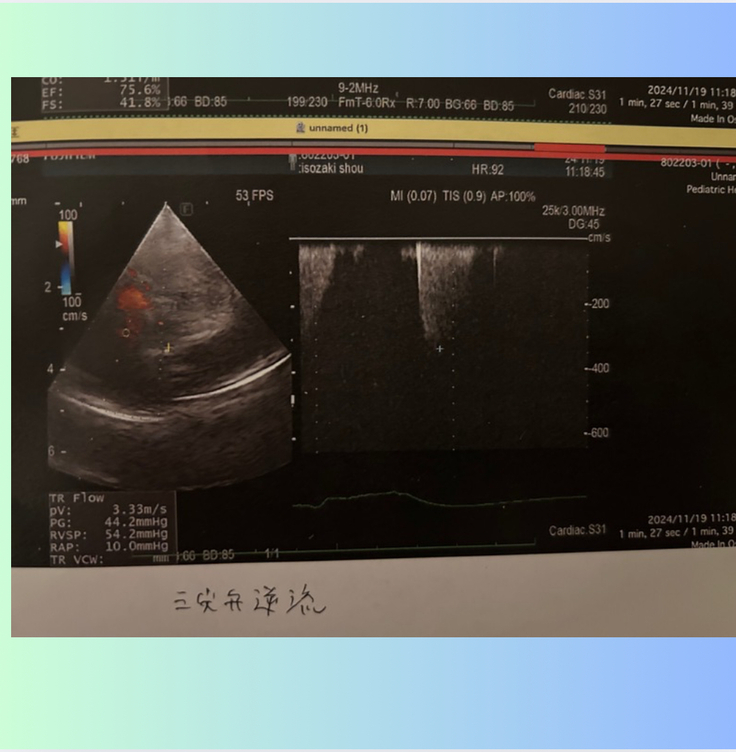

併発がわかった右心側の弁【三尖弁閉鎖不全症】は数値が前回より上がってしまっていました。

三尖弁の血液の逆流の数値が...

手術前は、 3.9m/s

退院時は、 3.4m/s

1ヶ月検診は、2.6m/s

2ヶ月検診は、3.3m/s